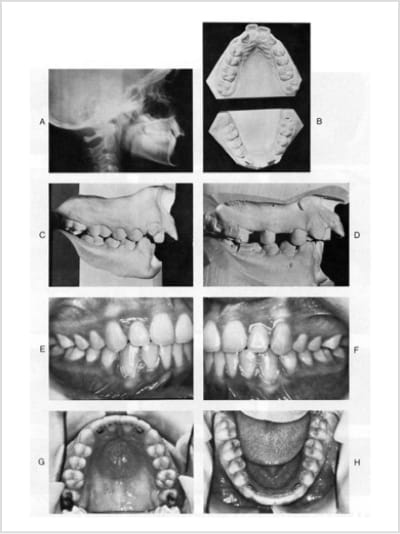

リップバンパーによるアーチデベロップメントを行い、臼歯の位置付けをただした結果、小臼歯非抜歯で配列出来た9歳の症例。

側方歯のアップライトで、口角部の隙間(バッカルコリドー)のないフルスマイル